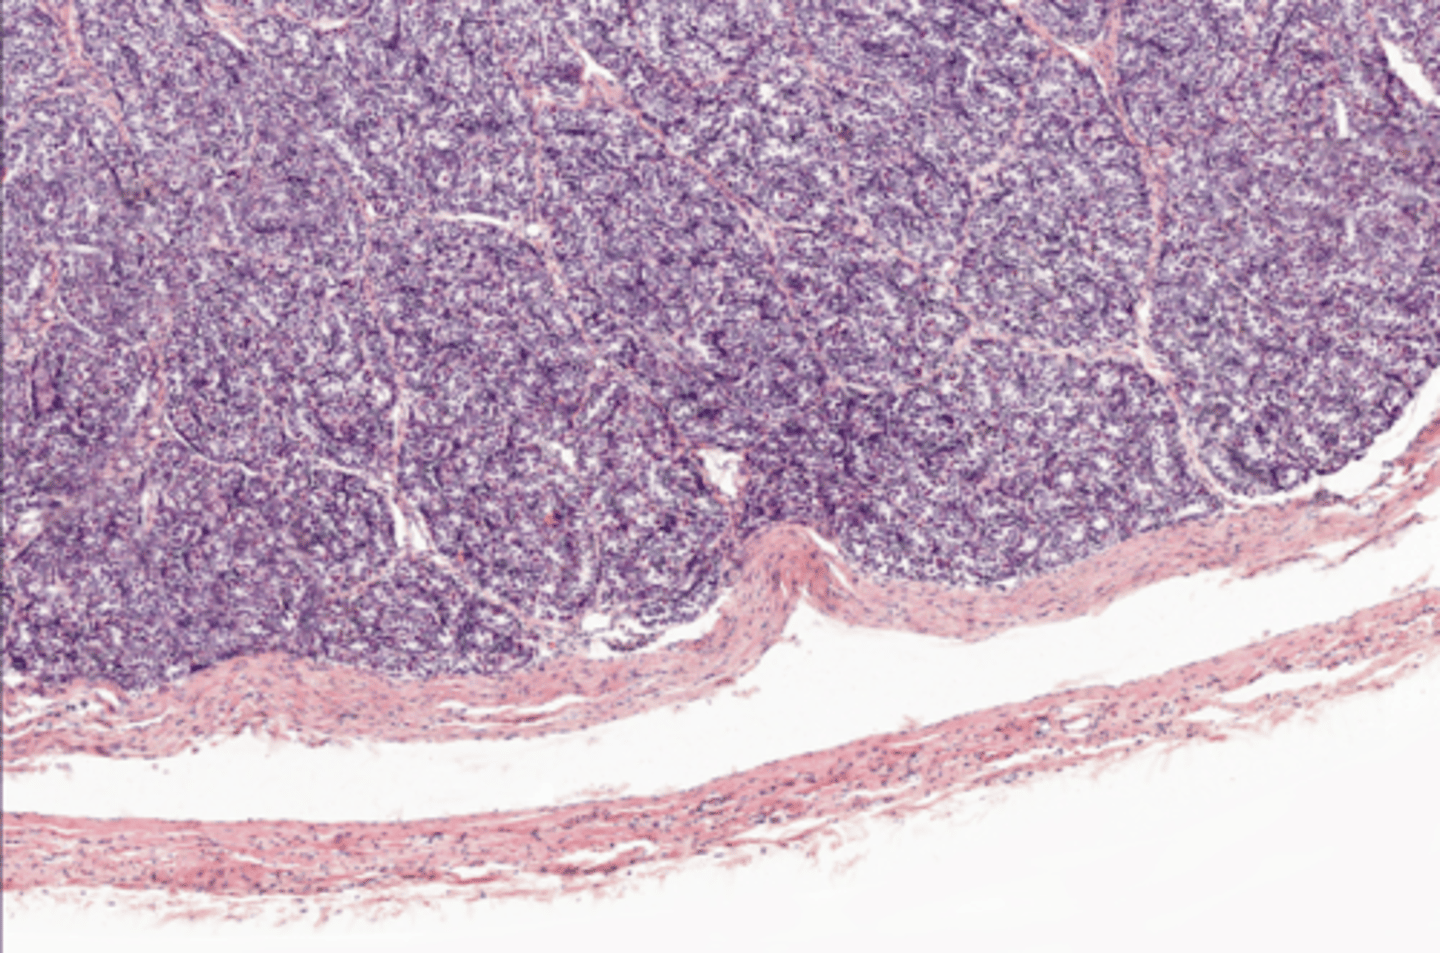

Seminiferous tubules

Seminiferous tubules

Seminiferous tubules